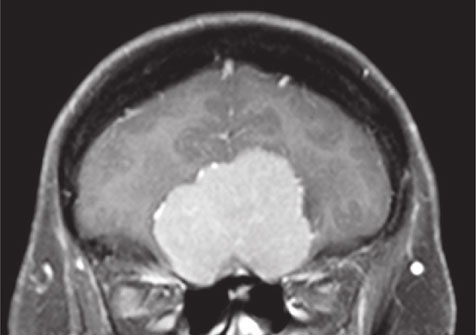

И это на самом деле так. Все повреждения передней части черепа могут нарушить их функционирование. На рисунке 36 можно видеть, как большая менингиома, доброкачественная опухоль, растущая из ткани, окружающей мозг, захватывает его именно в том месте, где обонятельные нервы проникают в череп. Естественно, что аносмия является обычным симптомом при заболеваниях подобного рода.

Рис. 36. Большая светло-серая масса, расположенная над носовыми полостями, это менингиома; в результате ее разрастания нарушается функционирование обонятельных нервов в том месте, где они проникают в череп